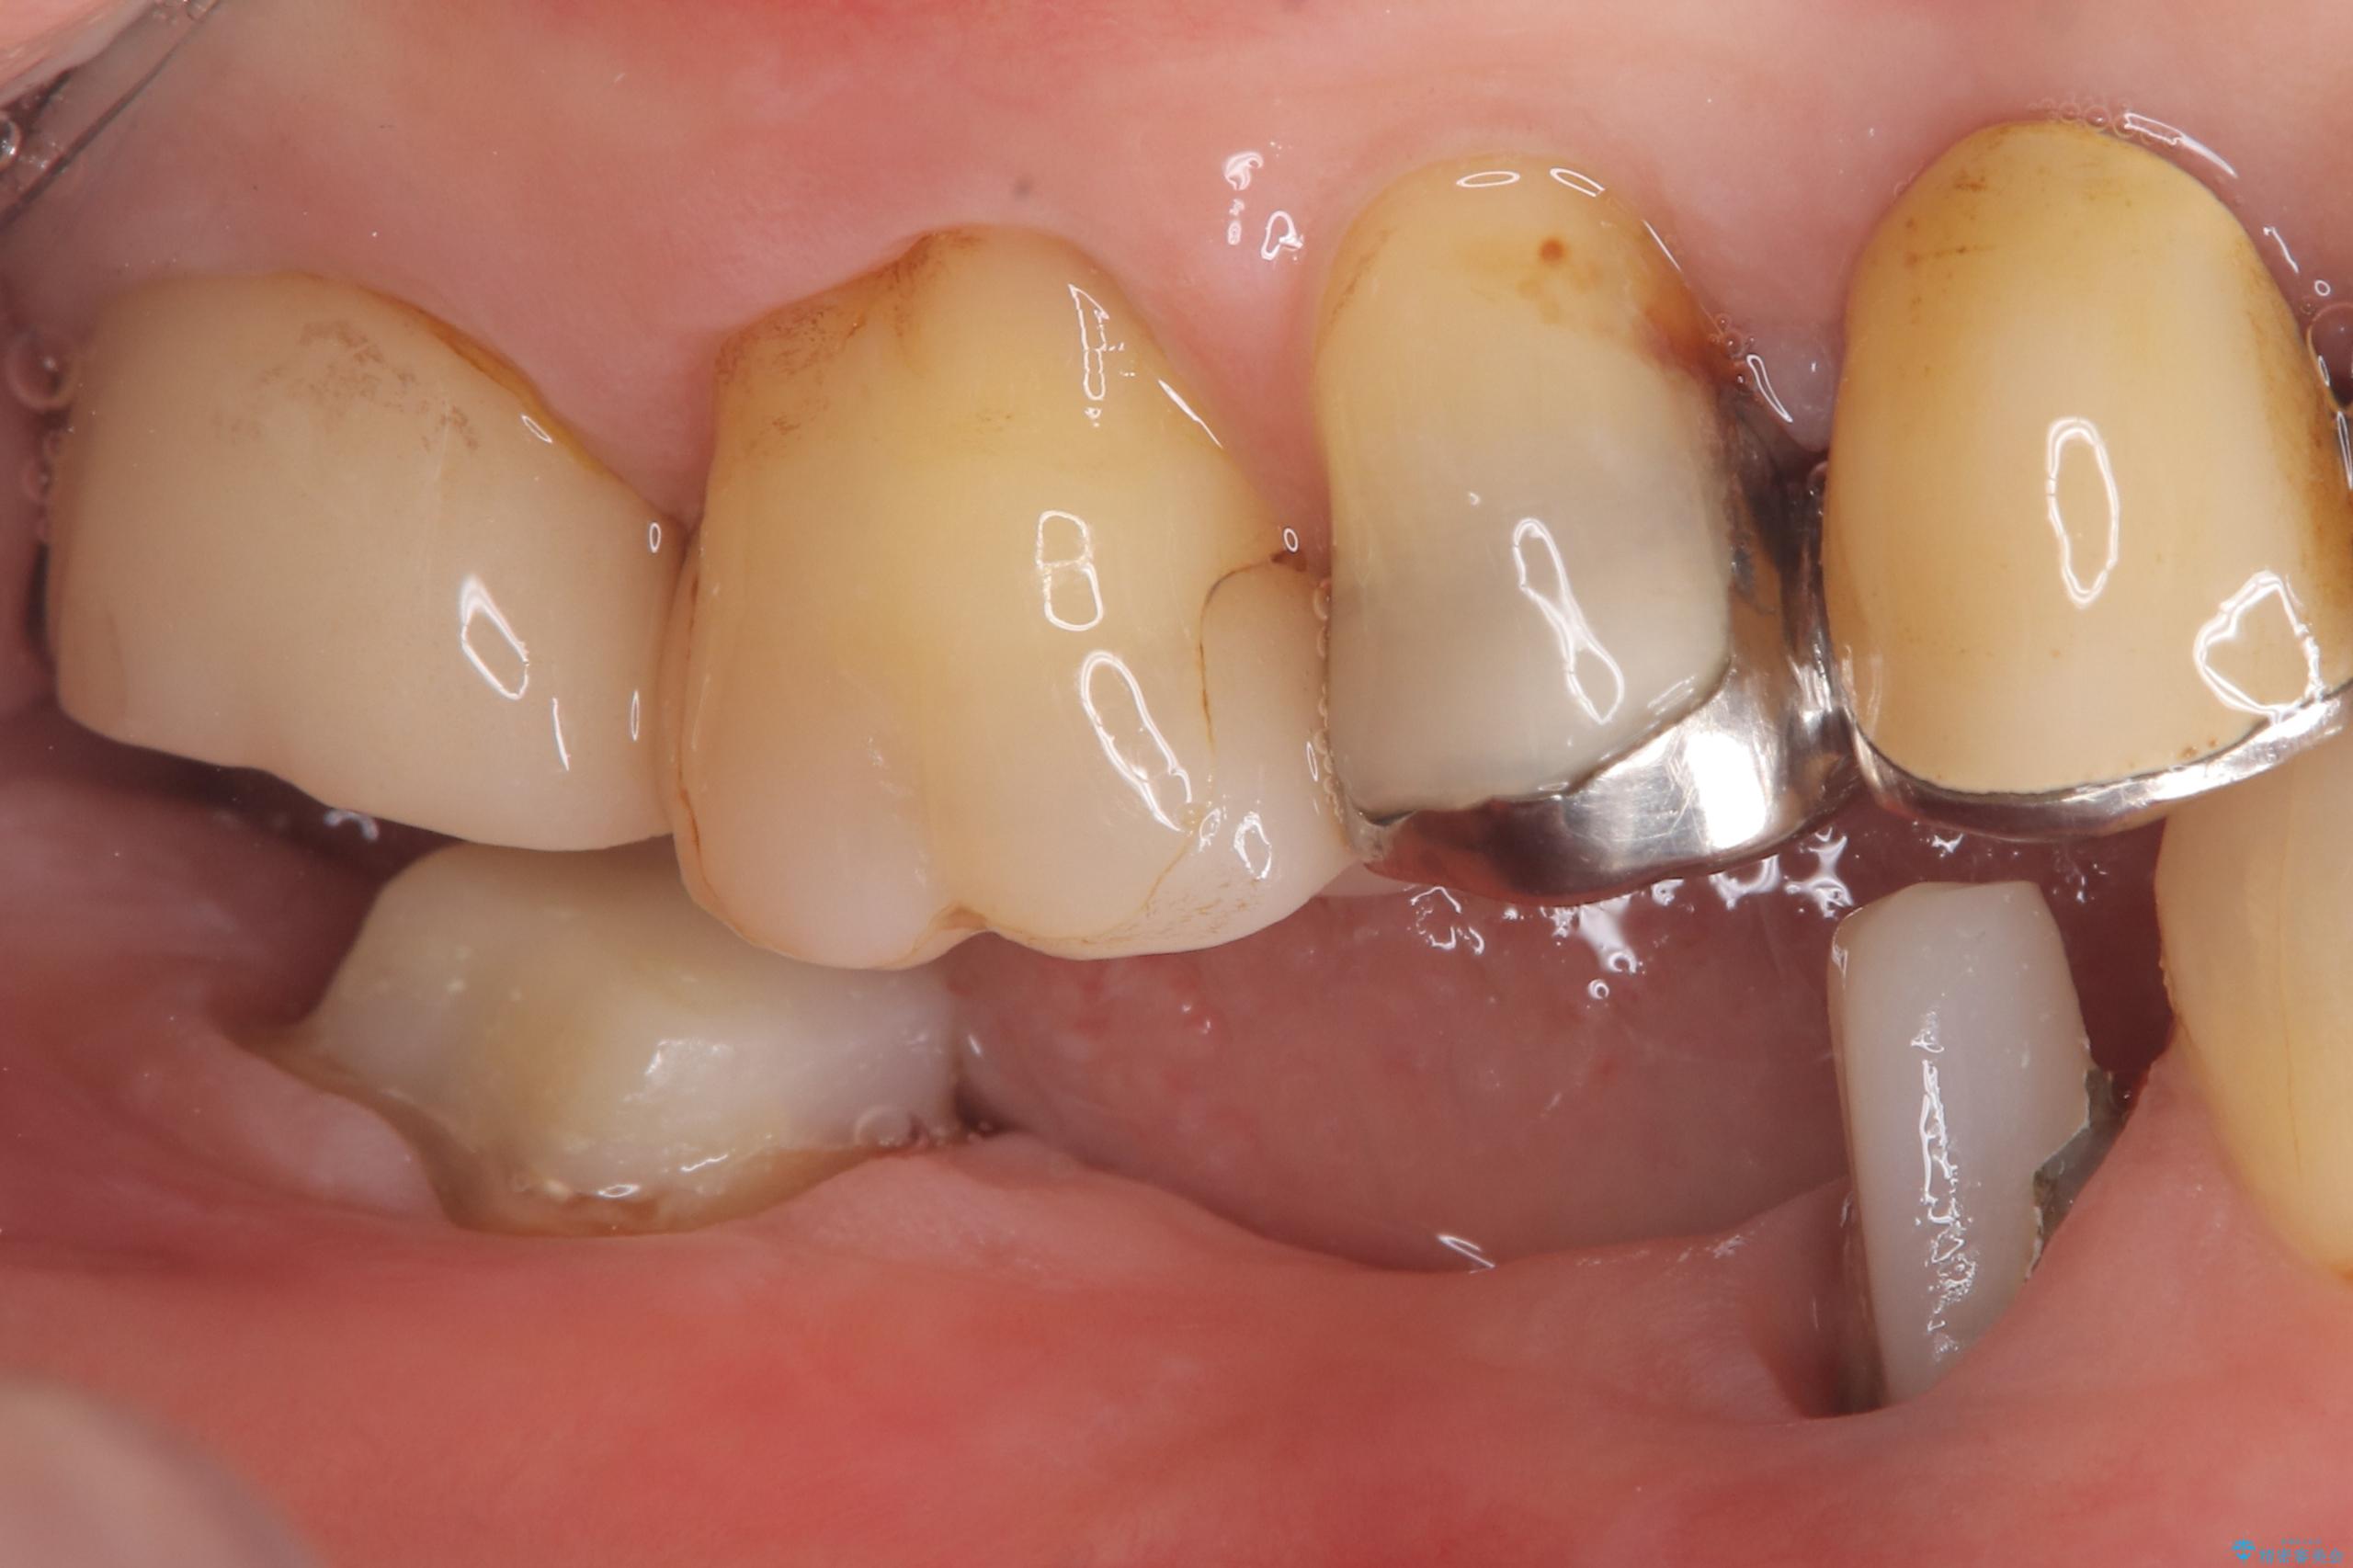

- 主訴:つい先日入れたセラミック(ジルコニア)ブリッジが奥歯部分で割れた。いつも同じ場所で壊れる。これで3度目。

セラミックに比べ、割れづらい金属(ゴールドでのブリッジのやり替えとなりました。

セラミックに比べ、破折リスクの少ない金属を使用したブリッジでのやり替えとなりました。

両支台歯が失活歯のため、どちらかもしくは両方の歯が破折した際、再度ブリッジを除去した治療が必要になるリスクとインプラント治療のご提案もさせていただきましたが、ブリッジでの治療を希望されました。

右下5番は支台歯CR築造を行っています。